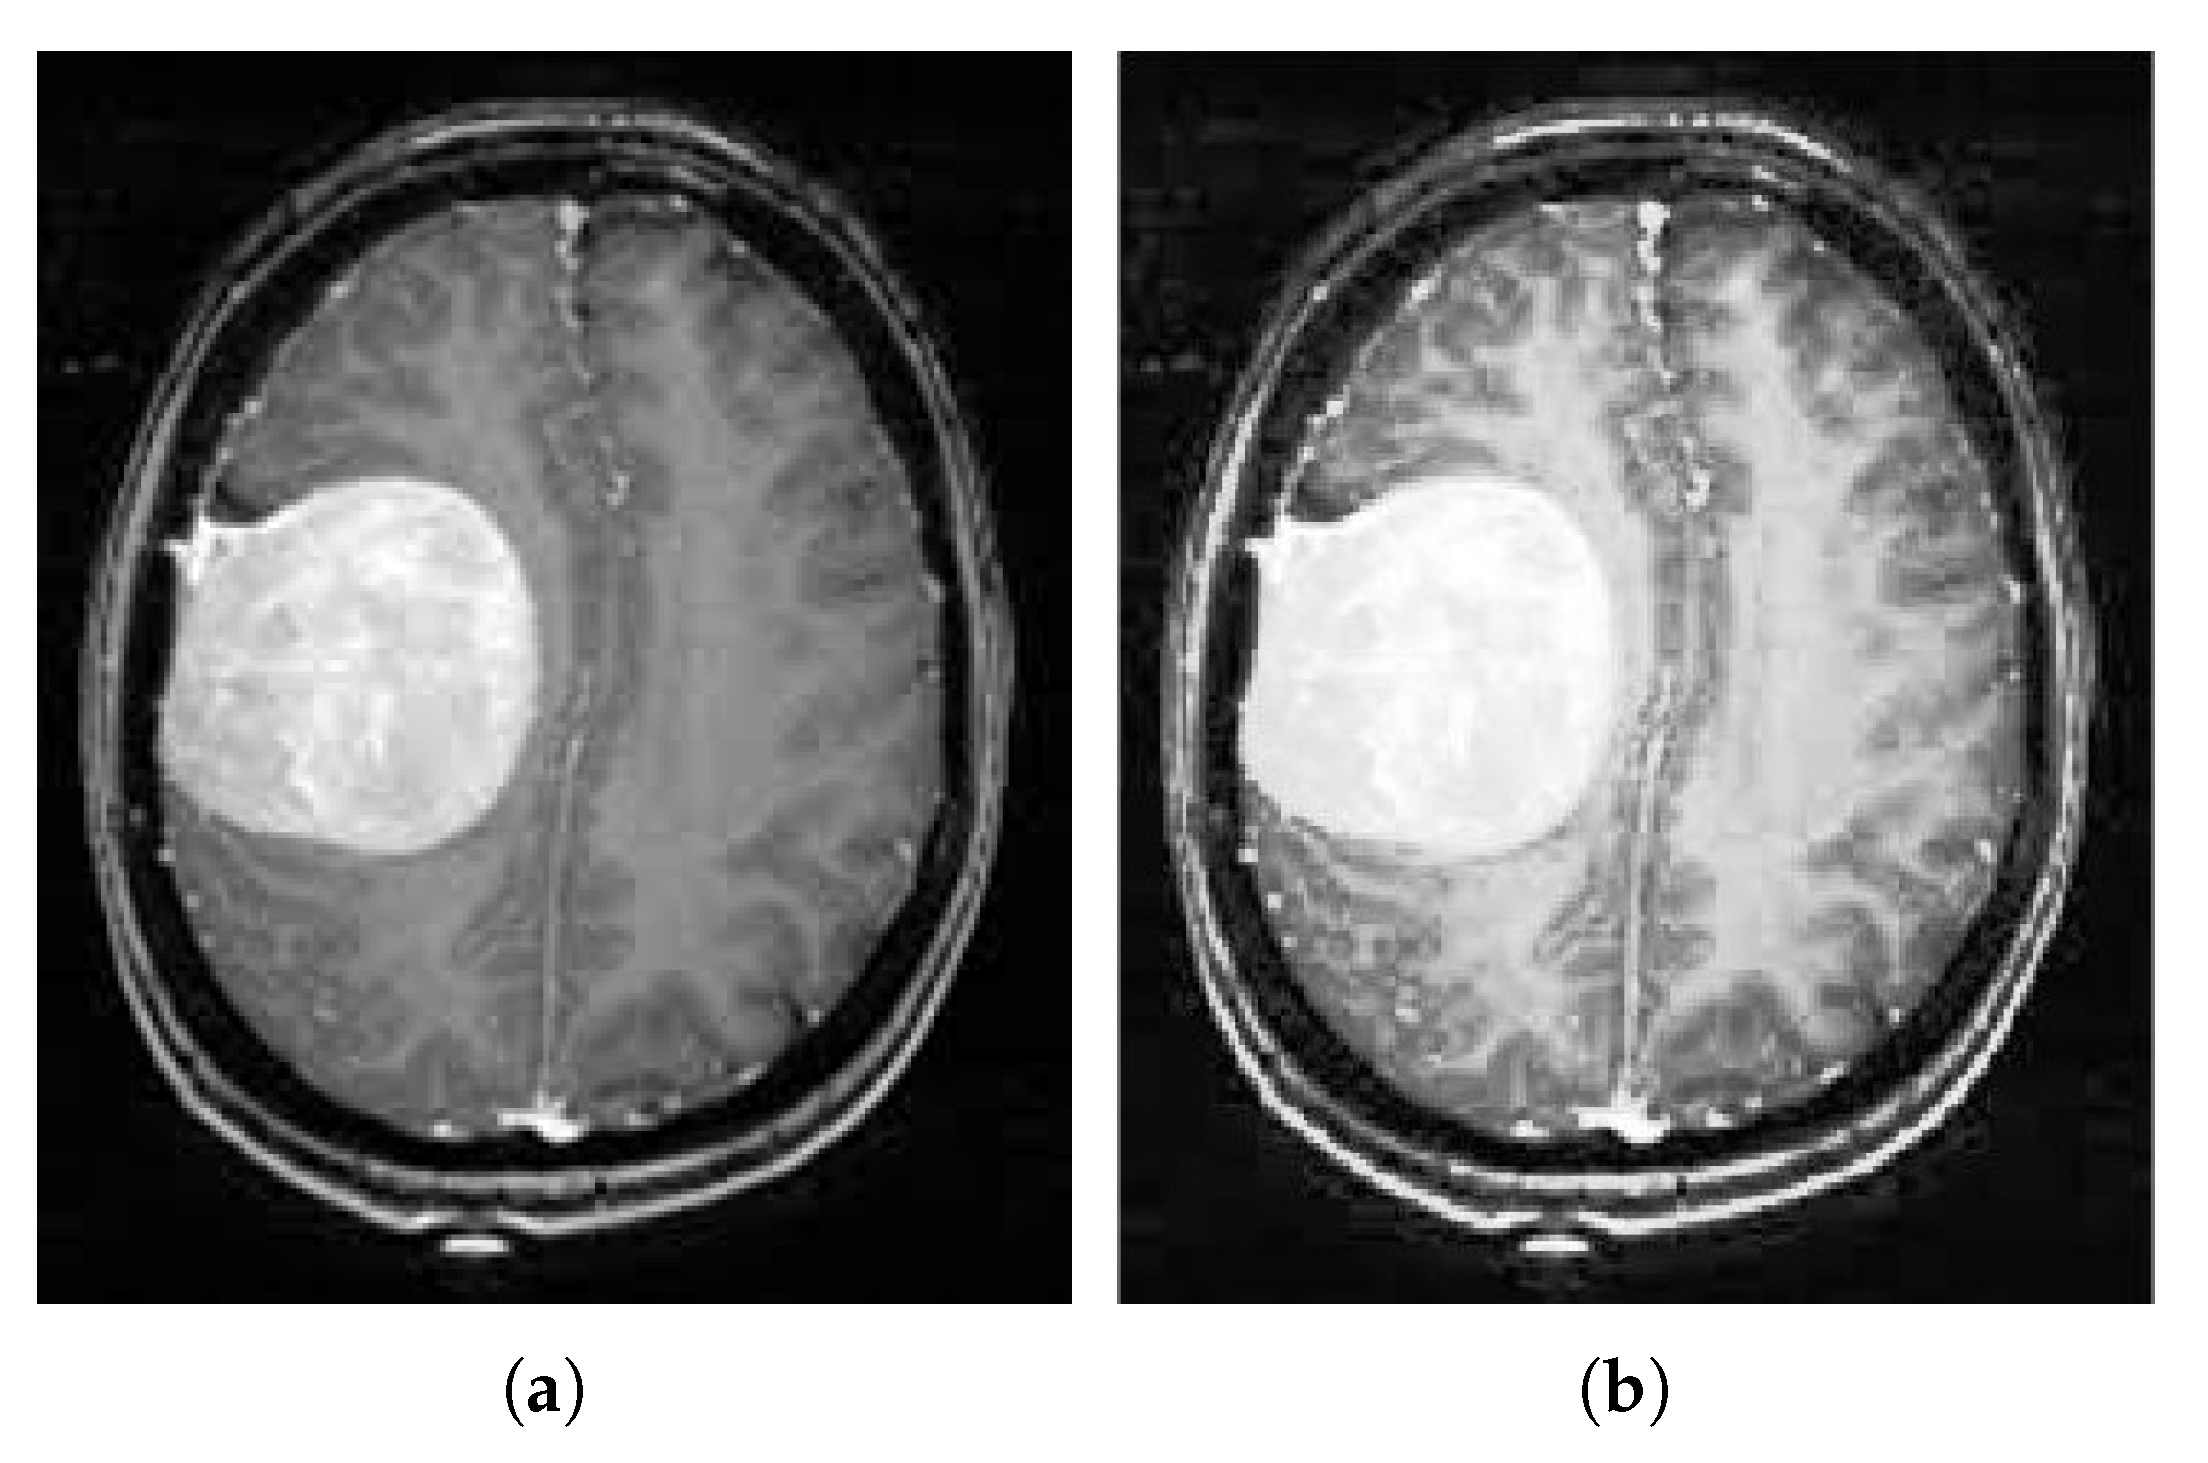

3.1. Contrast Enhancement

3.2. Tumor Segmentation